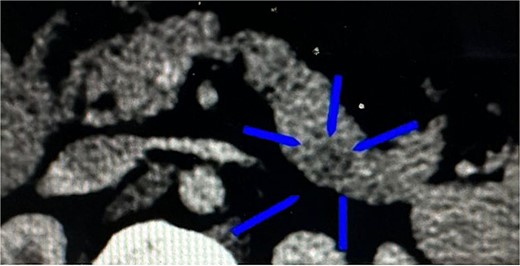

Once the above procedure was completed, it was dissected along the neck of the pancreas to identify the superior mesenteric vein and splenic vein. An incision was made along the superior border of the pancreas, to the left of the gastroduodenal artery and inferior to the hepatic artery. A plane was created between the portal vein and neck of the pancreas by blunt dissection from the inferior to the superior direction with a blunt-tipped laparoscopic dissector (Fig. 2).

A plane was created between the portal vein and the neck of the pancreas by blunt dissection.